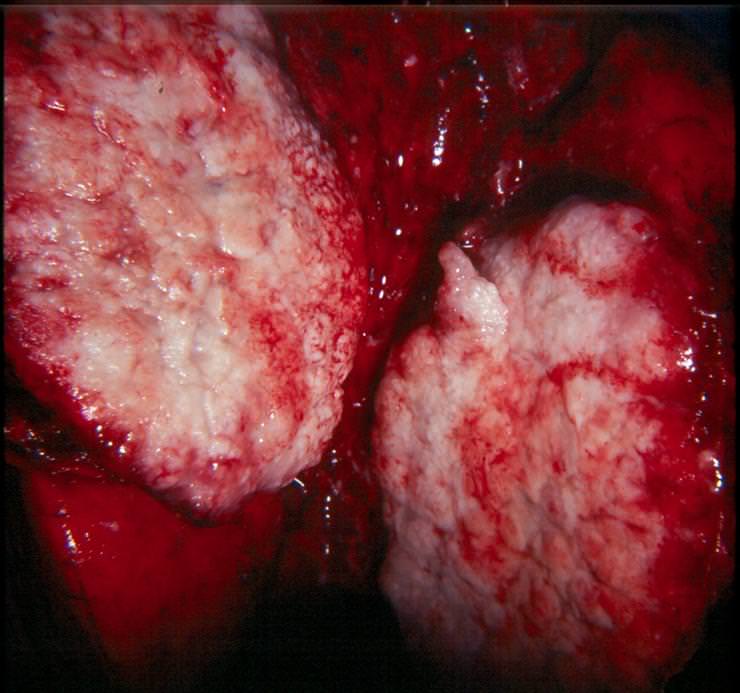

Для таких вот самоотверженных курильщиков, не щадящих живота своего, мы и представляем ряд наглядных материалов, иллюстрирующих изменения, происходящие в организме курящего человека. Быть может просмотр этой подборки заставит кого-то задуматься о том, во что превращается ваш организм под влиянием сигарет.

Рак легких

Легкие курильщика